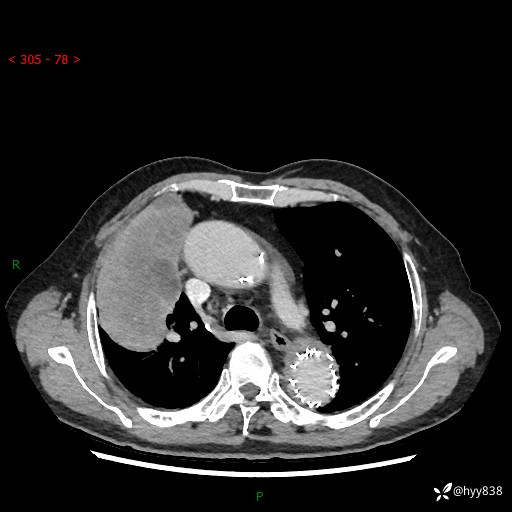

辅助检查:CT

胸部CT平扫

增强动脉期

静脉期